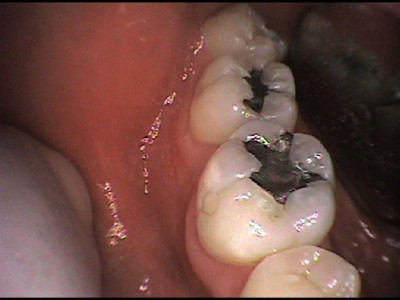

Cambio de amalgama a restauración estética

Envíado por Grupo Dental de El Salvador